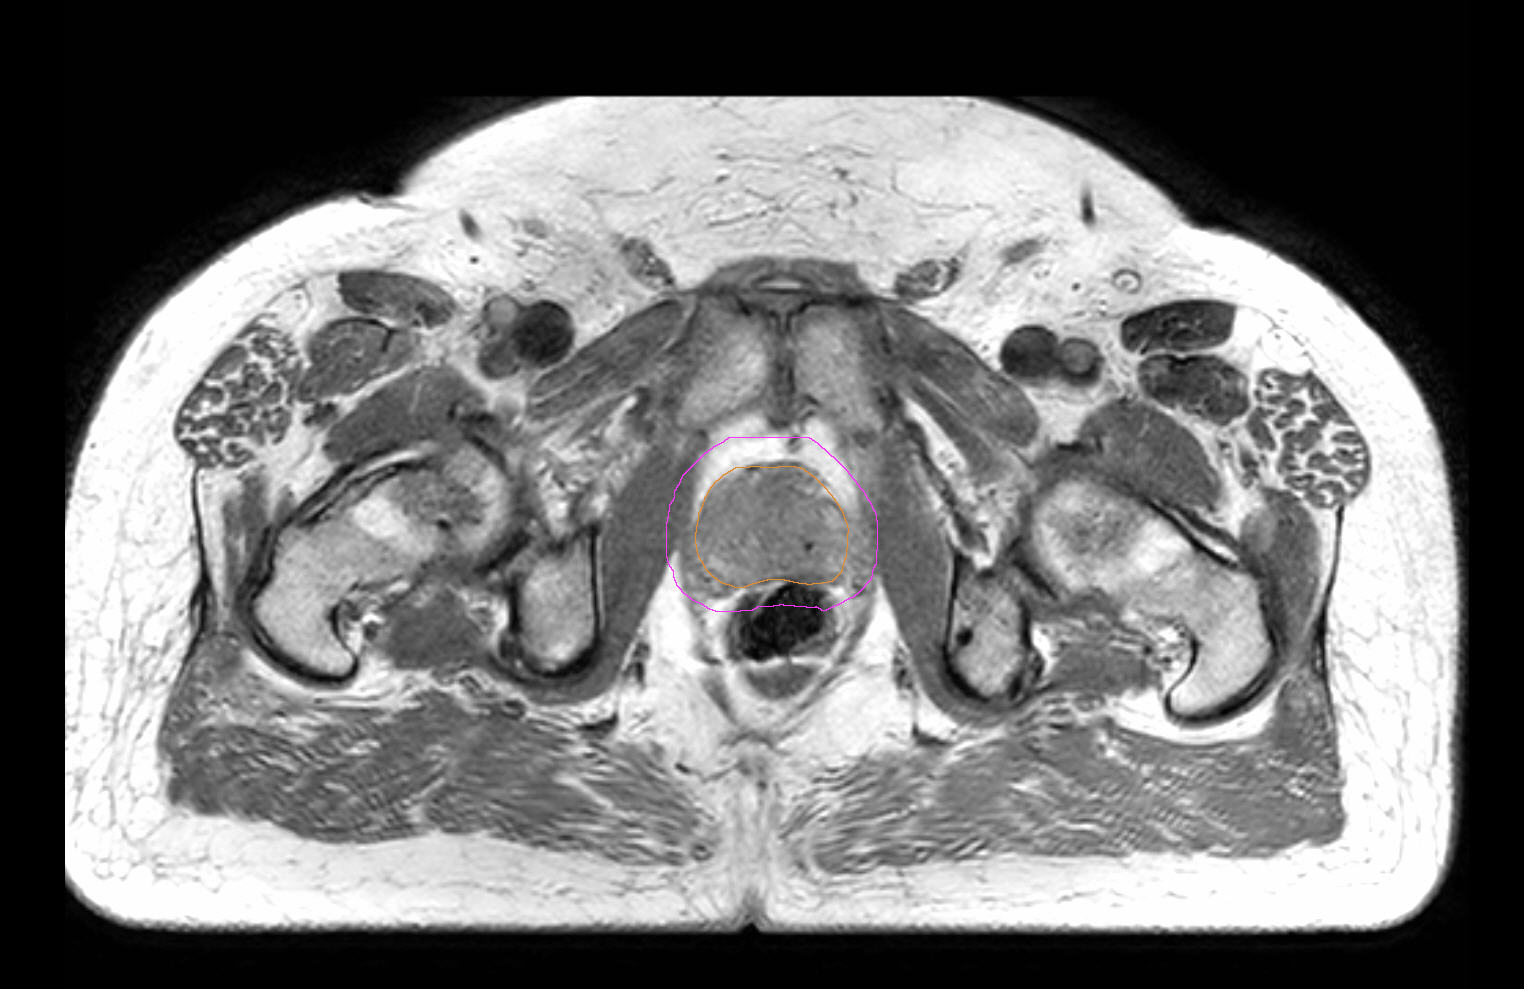

77-year-old male with prostate cancer cT3aN0M0, Gleason 8 and PSA 52 µg/L referred to androgen deprivation and radiation therapy with a prescribed dose of 50 Gy to the pelvic lymph node regions and 76 Gy to the prostate. Patient underwent MRI on Ingenia MR-RT 1.5T using FlexCoverage Anterior Coil in combination with the integrated Posterior Coil. Dose planning was performed on MRI imaging data.